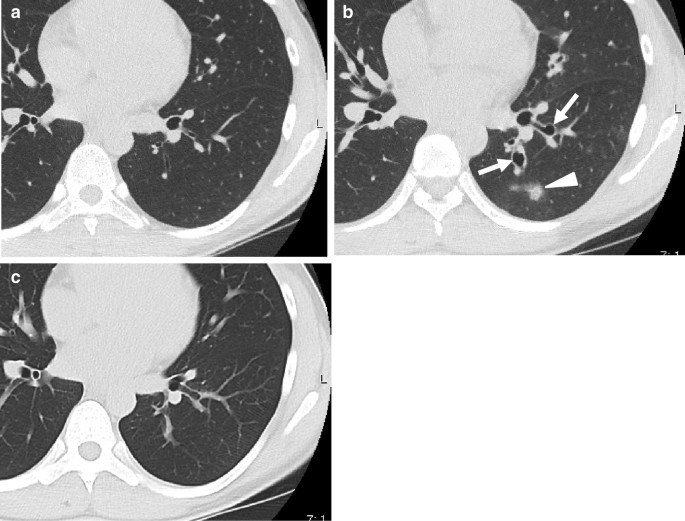

Chest computed tomography images. a Left lower lobe with thickened bronchial wall before bronchial thermoplasty (BT). b Saccular bronchodilation of left lower bronchus (B9, B10) (arrows) and nodular consolidation (triangle) are seen 3 weeks after BT. c Bronchodilation and consolidation are improved 5 months after the start of oral itraconazole administration

After the second BT session, she developed more sputum and cough. During the third session, white secretion and saccular bronchodilation appeared in the left lower bronchus (B9 and B10) (Fig. 2b). At the same time, bronchial washing was performed. Her CT also showed saccular bronchodilation in the affected bronchus (Fig. 1b). Aspergillus fumigatus was detected in the bronchial lavage culture. Oral itraconazole administration was started, and serum β-d-glucan and aspergillus antigen were found to be negative. Five months later, the subjective symptoms and CT findings improved (Fig. 1c). Although respiratory function remained unchanged (%FEV, 88%), exhaled nitric oxide reduced to 15 ppm. After BT, the inhaled steroid dose was reduced owing to a remarkable improvement in asthma symptoms. The patient was able to continue her cheerleading activity without exacerbations.

Chest computed tomography (CT) showed a thickened bronchial wall (Fig. 1a); the percentage forced expiratory volume (%FEV) was 86.2%, and exhaled nitric oxide was 45 ppm. Blood test results revealed the following: 515 U/mL, IgE; 8900/μL, white blood cell count; and 143/μL, eosinophils. The patient received 30 mg/day prednisolone for 3 days before BT treatment and continued it for 1 day post-BT treatment. The sessions for the right and left lower lobe were properly completed at 3-week intervals, and the BT activation numbers were 31 and 24 times, respectively (Fig. 2a).